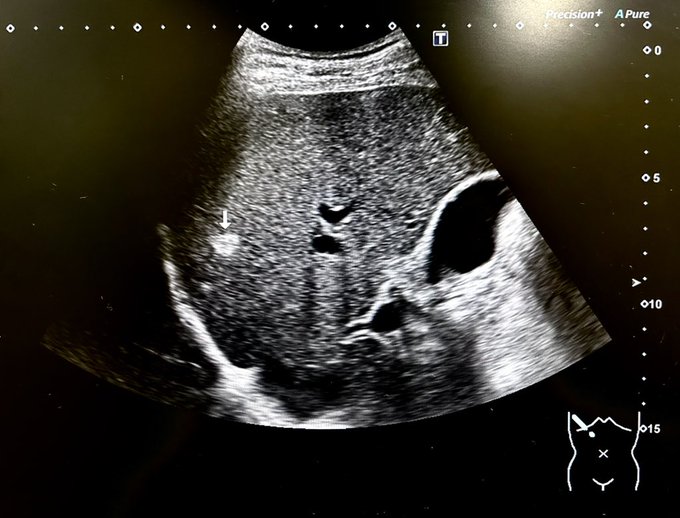

本日は病院へ。過日のエコー検査と造影剤を注入してのCT検査、それらを受けての診断。肝臓に見つかった約9mmの血管腫(写真参照)は、良性のものと判明!良かった、良かった。ただ、初めて確認されたものなので..